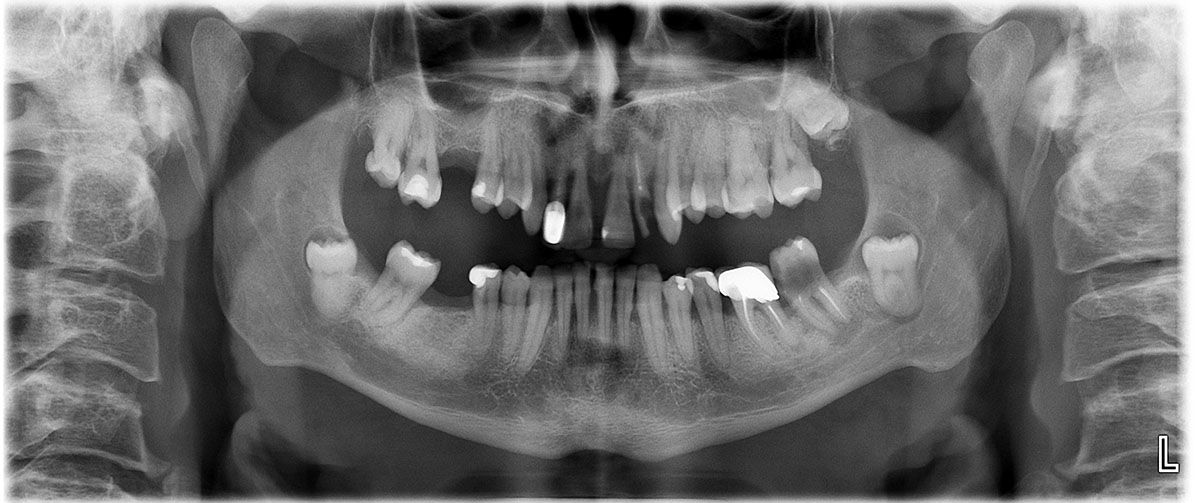

Случай 3: Лечение с импланти